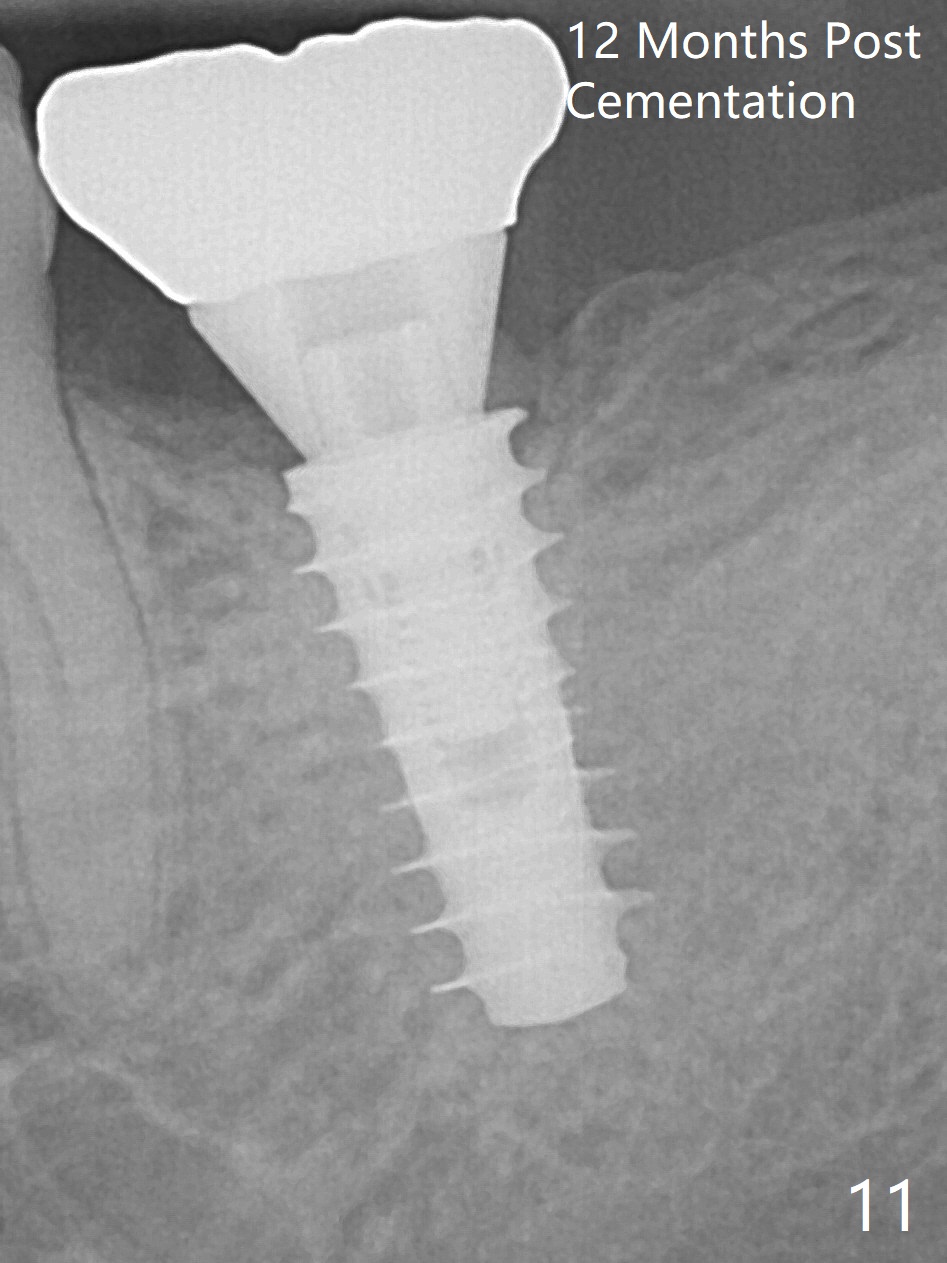

Trabeculae form in the used-to-be distal socket 12 months post cementation (17 months postop, Fig.11). In spite of this, the patient complains of mastication pain.